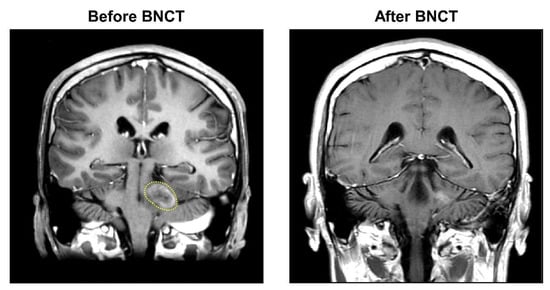

3.1.3. Case 3 (Patient #7)

| 7 | 30 | M | Glioblastoma | Focal | 70 | 1.59 | 3.83 | 2.22 | 22.85 | 10.95 | 7.24 | 18.20 | 3.83 | 2.22 | 26.95 | 9.68 | 6.38 | 16.17 | CR | No | No |